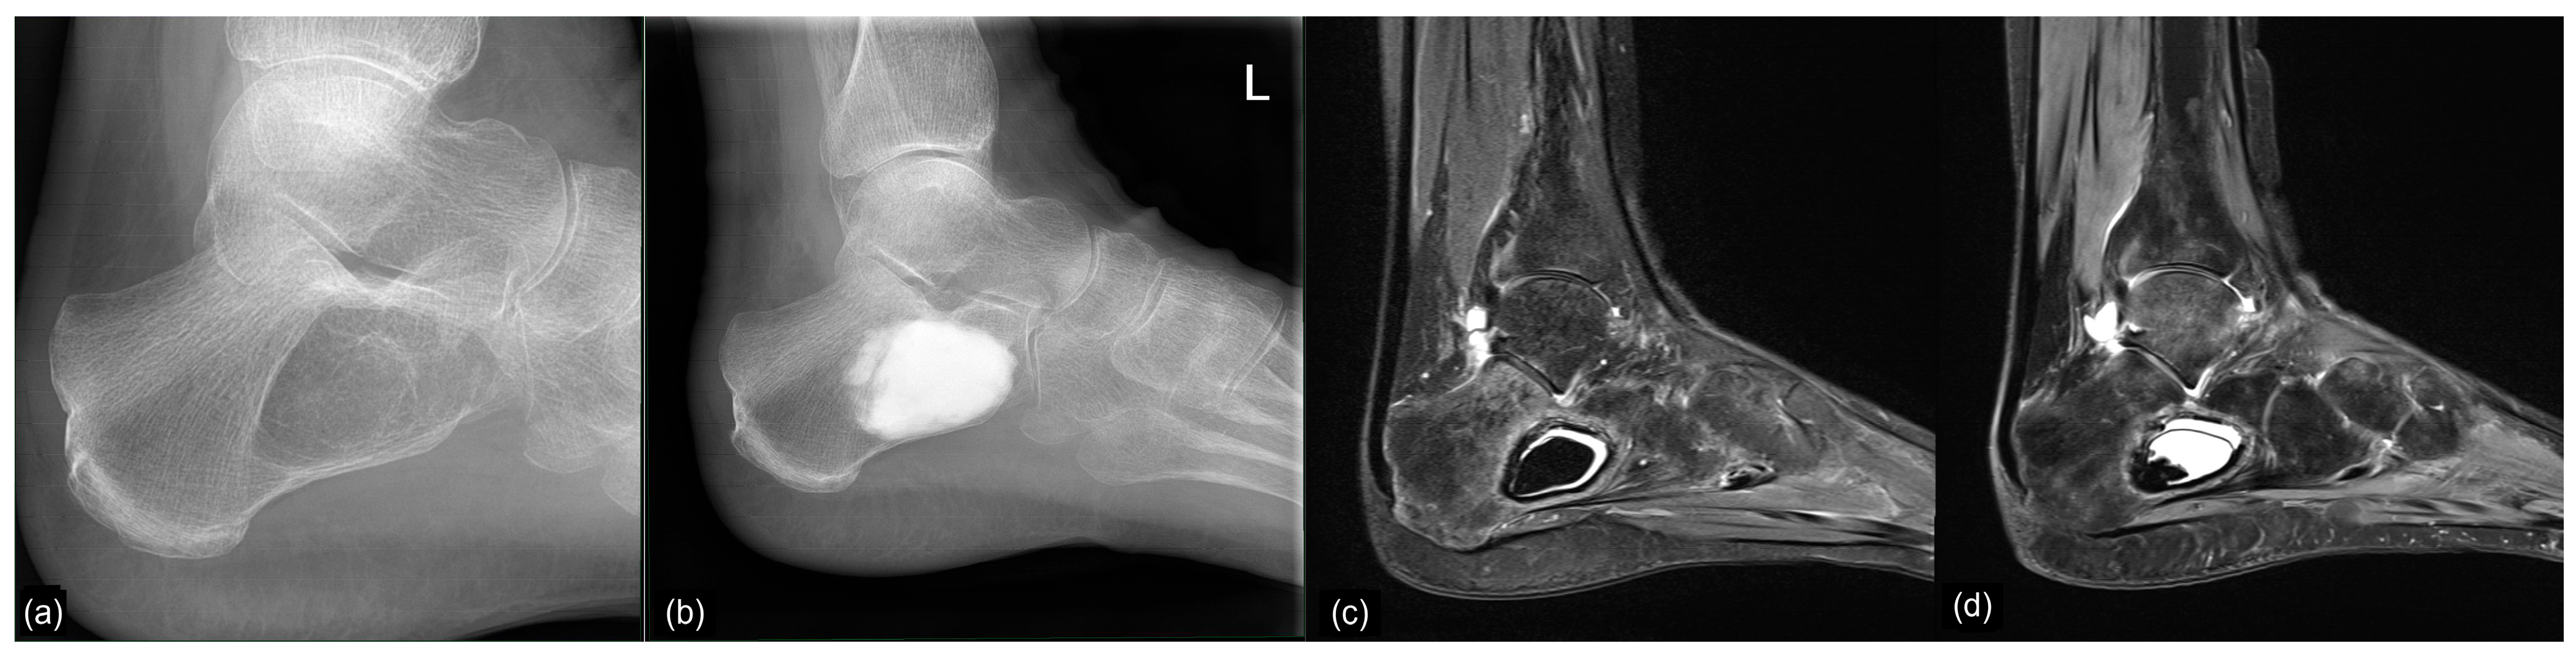

Preoperative imaging with plain radiographs and MRI led to the diagnosis of 17 SBCs and eight IOLs. Both entities exhibited a characteristic, almost pathognomonic appearance on MRI, making bioptic verification of the diagnosis unnecessary. Often times, MRI revealed a mixed form of SBC and IOL, showing lipomatous tissue enclosing central cystic areas (Figure 8). This has been commonly described as the evolution of an IOL (Milgram Stage 3 []) or involution from other preexisting bone lesions [,,,], suggesting that IOL develops from precursor lesions. It should be noted that in the current 2020 edition of the WHO classification of soft tissue and bone tumors, SBC and IOL are listed as separate entities and their etiology is considered unknown []. However, several publications have documented the transition of SBC to IOL over time, suggesting that IOL may actually represent a developmental form of SBC [,,,].

Figure 8.

Preoperative MRI of case 12 (19-year-old male patient) showing a calcaneal IOL with cystic changes corresponding to a Milgram Stage 3 type []. However, histopathological examination of the tissue samples taken from the bone cavity revealed SBC.

Two cases initially diagnosed as IOLs based on MRI turned out to be SBC in the histopathological analysis (case 5 and 12). Another case of suspected IOL demonstrated membranous material with a histiocyte-resorptive reaction but no cholesterol clefts (which are typical for SBC) upon histopathological evaluation, resembling SBC (case 10).

Both our endoscopic and histopathological results support the theory proposed by other authors such as Malghem, Tins, and Kawaguchi that (calcaneal) IOL develops form SBC [,,,].